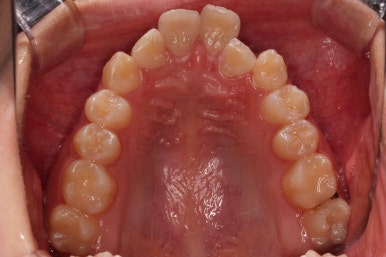

동래교정치과 초진 시의 입 안 모습이에요.

치열이 삐뚤고 덧니가 보이네요.

이번 환자분도 스스로는 보기 싫은 이유가 첫 번째였지만 사진에서도 보시다시피 양치가 잘 안되어 치석도 많고 잇몸도 부어있는 상태였어요.

그리고 앞니들이 마모가 많이 되어 있어서 각각의 치아들이 원래 형태에서 많이 변형된 것을 볼 수 있네요.

장치를 부착했어요.

윗니는 상대적으로 많이 보이기 때문에 세라믹, 아랫니는 많이 보이지 않기 때문에 메탈로 부착했어요.

치여링 가지런해졌고, 교합과 중앙선 등 입안의 모습이 매우 좋아졌어요.

불규칙하게 마모되어 있던 치아의 개별 형태도 약간씩 다듬어 드렸고요.